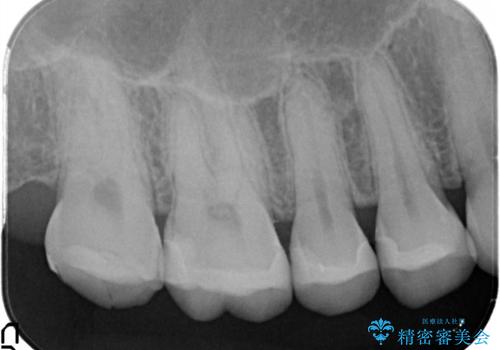

- 金属の詰め物を外して、セラミックインレーを入れたいと来院された患者様です。

奥歯に虫歯も認め、3歯の治療を来院回数2回で終了で終了しています。

当院でのセラミックインレーはすべてe-maxと呼ばれる高強度セラミックにて製作されます。

また、製作方法もプレスと呼ばれる方法を用いることで精度を高めています。